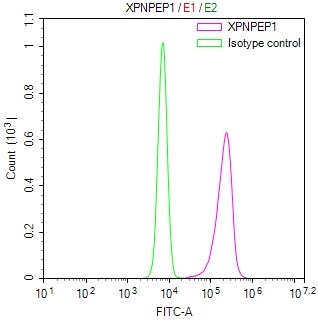

圖片: